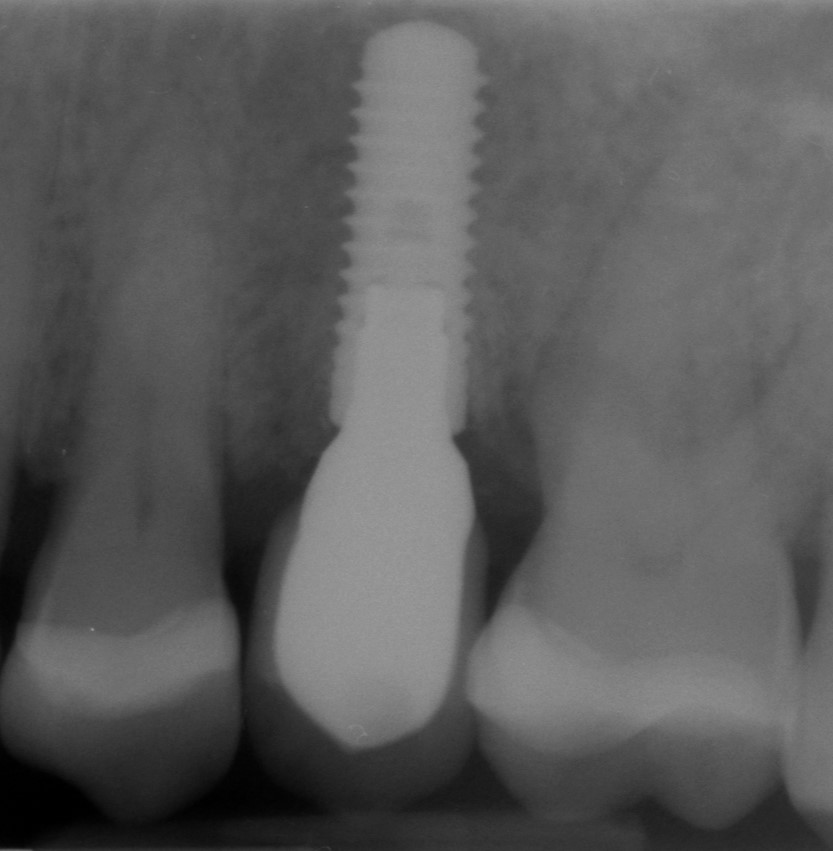

Implant insertion in atrophic alveolar ridge